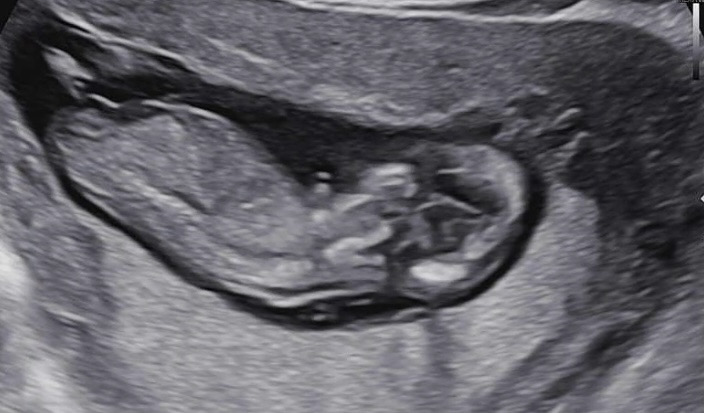

12주 1일차 성별 어떻게 보시나요?~

아들딸 상관은 없는데 아기형태 보고오니 막상 궁금해지네용ㅋㅋㅋ